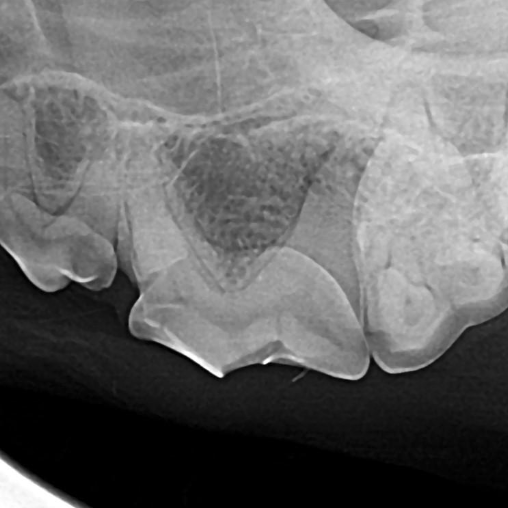

Example of a fractured triple-rooted tooth in a dog:

Before: